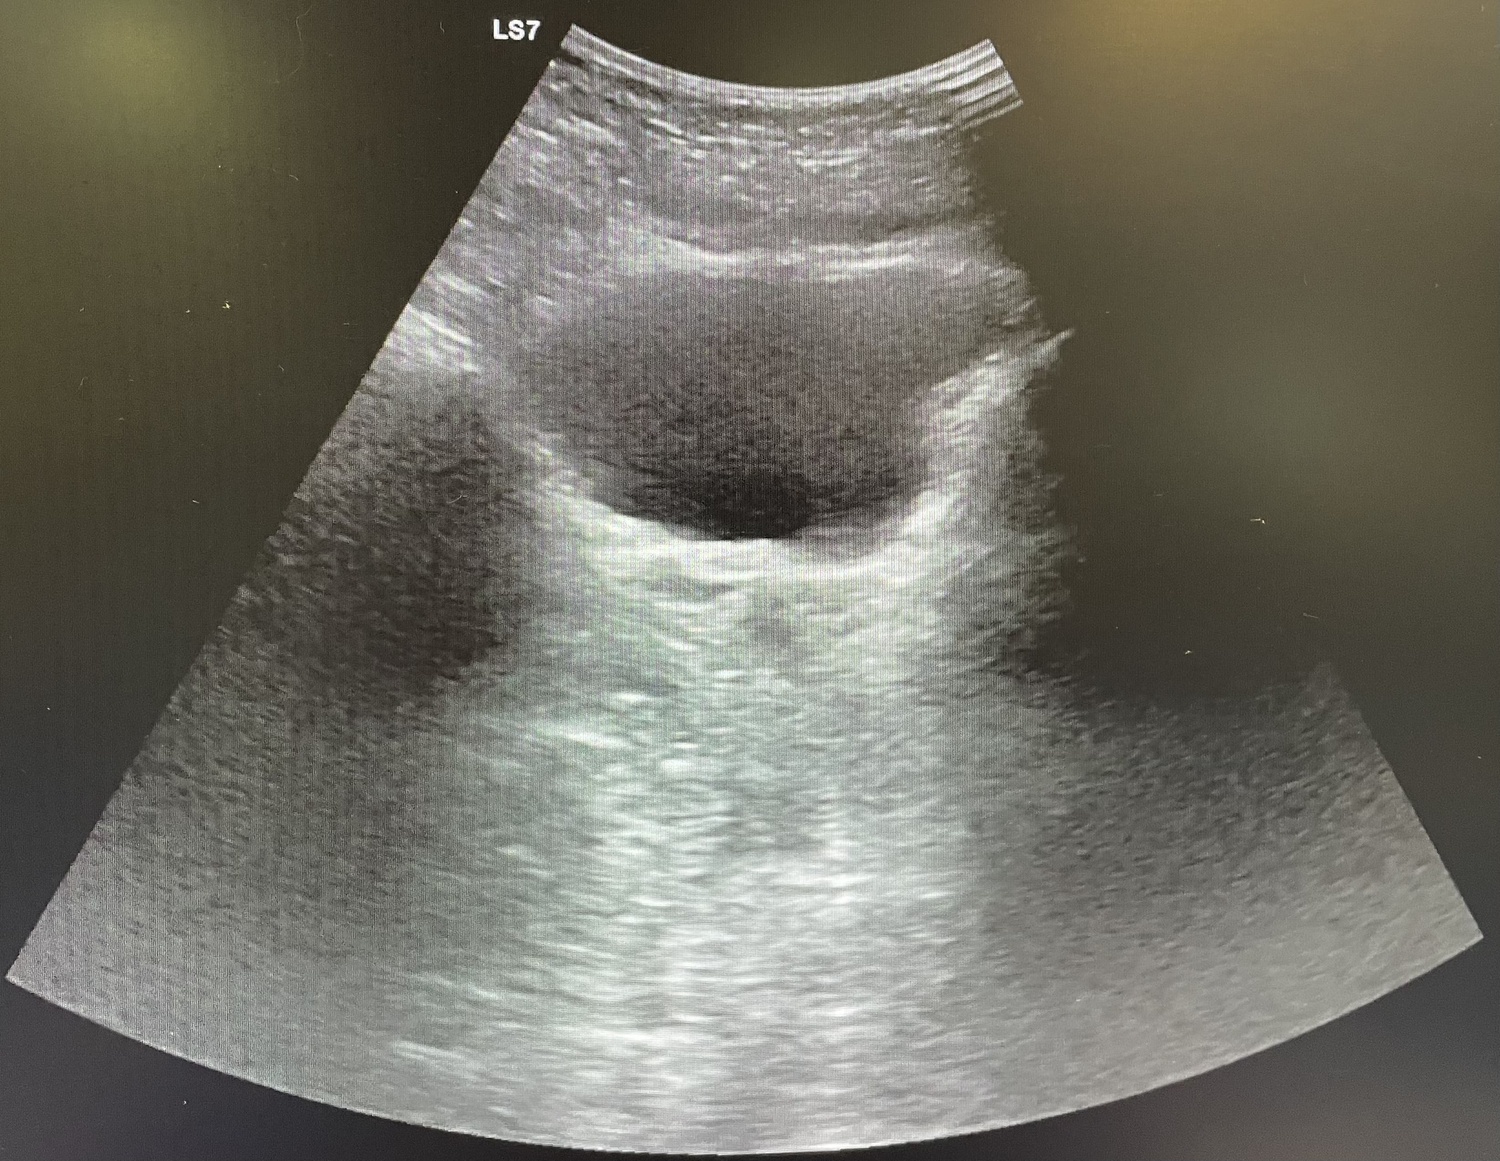

Durante el ingreso la paciente presenta mejoría de la clínica, además de disminución de reactantes de fase aguda en analítica y ecográficamente sin peor evolución. Después de 3 días de ingreso se procede al alta a domicilio con antibioterapia oral y consulta de revisión ambulatoria.